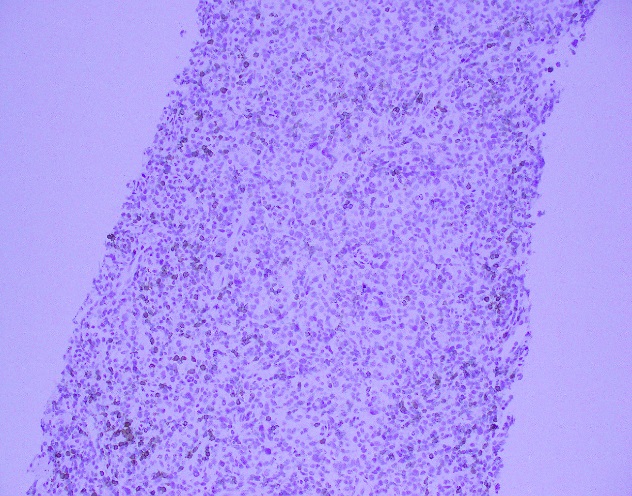

The core needle biopsy material demonstrated a lymphoid population that was polymorphic in appearance with medium to large sized lymphocytes with moderate amounts of pale cytoplasm, irregular nuclei, vesicular chromatin, and some cells with prominent nucleoli. The background cellular population is composed of a mixed inflammatory component including small lymphocytes, scattered neutrophils, eosinophils, and histiocytes.

By immunohistochemistry, the medium to large sized cells with pale cytoplasm are positive for CD3, CD2, CD4, and CD5 with complete loss of CD7. CD20 highlights scattered background B-cells. CD21 is positive in disrupted follicular dendritic meshworks. CD10 and BCL6 are negative in neoplastic cells. PD1 is positive in neoplastic cells with a subset co-expressing CXCL13. By Ki-67 immunostaining, the proliferation index is 50-70%. By in situ hybridization for Epstein-Barr virus encoded RNA, a subset of cells are positive.

Overall, with the morphologic and immunophenotypic features present, the diagnosis is that of angioimmunoblastic T-cell lymphoma.